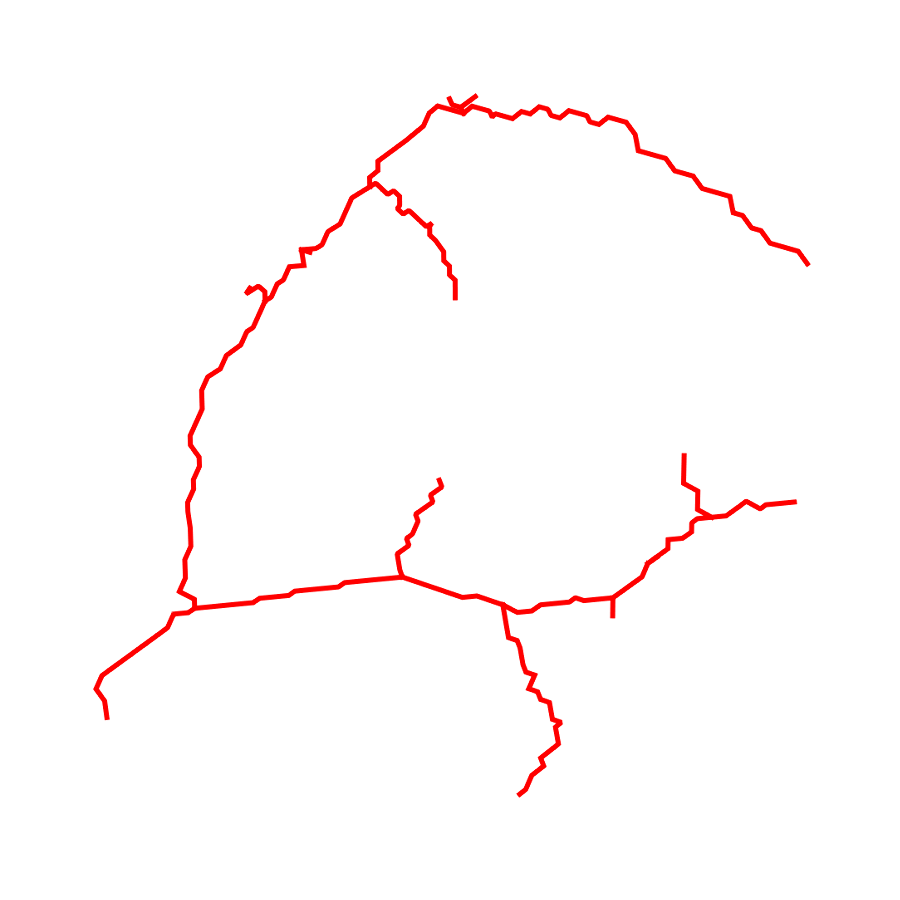

3.1 Connectedness of the Vesselness Map

Fig. 3 shows the connectedness of vessels recovered from state-of-the-art vascular enhancers and curvilinear ridge detectors FFR and OOF together with the proposed CVM for the synthetic HCP and the real PC images.

On the synthetic phantom, FFR shows a fragmented and rough vesselness response in correspondence of irregularly shaped sections of the structure. Also, the response at the bifurcation is not smoothly connected with the branches (triangular loop). Conversely, OOF recovers the phantom connectedness at the branch-point, and the vesselness response is consistent along the tortuous curvilinear section, however ghosting artifacts are observed as the shape of the phantom becomes irregular (C-like) or differs from a cylindrical tube. Also, close convoluted structures, which change scale rapidly in the HCP, produce inconsistent responses of OOF (fig. 3). CVM shows here a strongly connected vesselness response in correspondence of both regular and irregular tubular sections, with local maxima at structures’ mid-line. The connectedness of the structures is emphasized regardless the complexity of the shape, and it resolves spatially the tortuous curvilinear ‘kissing vessels’ without additional ghosting artifacts, despite the smooth profile.

Similar results are observed on the PC dataset: FFR has a poor connected response in the noisy and low-resolution image. Vessels are overall enhanced, however thin and fragmented structures remain disconnected. Overall, the vesselness response is not uniform within the noisy structures, where maximal values are often off-centred. A more consistent response is obtained from OOF, where the connectedness of vessels is improved. Maximal response is observed at the mid-line of vessels, however, noise rejection is poor. CVM strongly enhances here the vessel connectivity. The fragmented vessels of PC have a continuous and smooth response in CVM with higher values and a more defined profile. Large vessels shows solid connected regions with local maxima at mid-line as in OOF. Conversely from OOF, CVM shows improved noise rejection in the background.

The respective tensor fields (TF) synthesized on both HCP and PC show consistent features. The TF’s characteristics are in line with the connectedness of CVM: enhanced and connected vessels are associated with high anisotropy, whereas background areas show a predominant isotropic component.